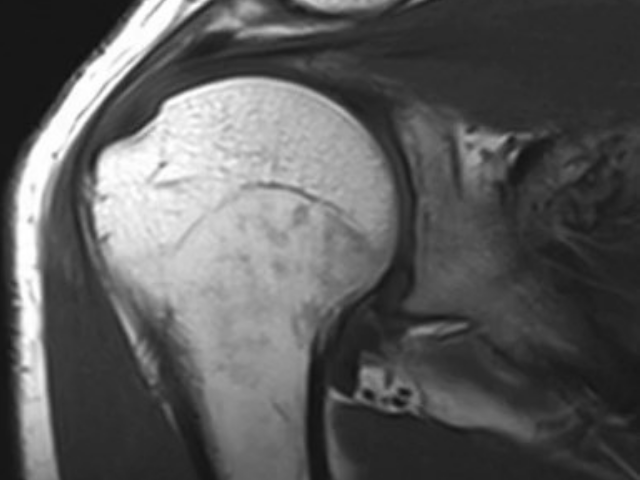

五十肩(肩関節周囲炎)は、肩の関節を囲む組織に炎症が起こり、痛みや動きの制限が生じる状態です。40〜60代に多く見られますが、必ずしも50代に限った症状ではありません。特徴的な症状として、夜間の痛み、腕が上がりにくい、後ろに手が回しにくいなどがあります。多くの場合、徐々に症状が進行し、適切なケアをしないまま放置すると、症状が長引くことがあります。